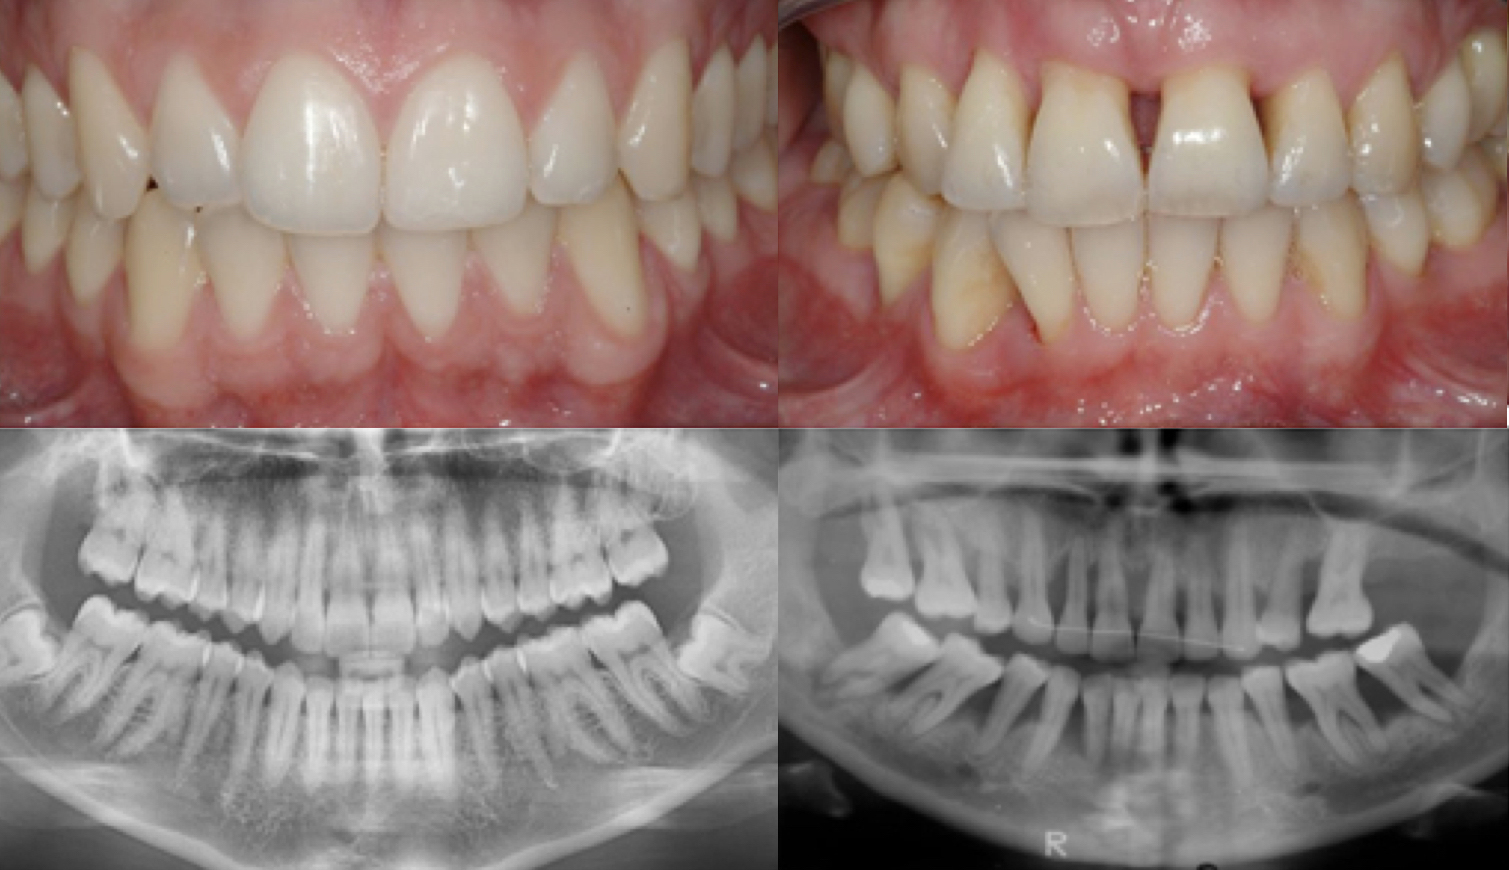

Parodontitis ist eine schwere Zahnfleischentzündung, die das Weichgewebe schädigt und den Knochen zerstört, der Ihre Zähne stützt. Parodontitis kann dazu führen, dass sich die Zähne lockern und kann zum Zahnverlust führen. Parodontitis ist häufig, aber weitgehend vermeidbar. Dies ist in der Regel das Ergebnis von unzureichender Mundhygiene ohne Zahnzwischenraumbürstchen und Zahnseide. Mindestens zweimal täglich bürsten, täglich Zahnzwischenraumbürstchen und Zahnseide verwenden und regelmäßige zahnärztliche Untersuchungen durchführen, kann Ihre Chancen auf eine erfolgreiche Behandlung von Parodontitis bzw. Zahnfleischentzündung erheblich verbessern und auch die Entstehung von entzündetem Zahnfleisch verringern.

Gesundes Zahnfleisch ist fest und blassrosa und sitzt eng an den Zähnen. Anzeichen und Symptome einer Parodontitis können sein:

- Geschwollenes Zahnfleisch

- Helles rotes, dunkelrotes oder violettes Zahnfleisch

- Zahnfleisch, das sich bei Berührung weich anfühlt

- Zahnfleisch, das leicht blutet

- Zahnfleisch, das sich von den Zähnen wegzieht, wodurch Ihre Zähne länger aussehen als normal

- Neue Räume entstehen zwischen den Zähnen

- Eiter zwischen Zähnen und Zahnfleisch

- Schlechter Atem

- Zahnverlust

- Schmerzhaftes Kauen

- Eine Änderung in der Art und Weise, wie Ihre Zähne beim

- Beißen zusammenpassen